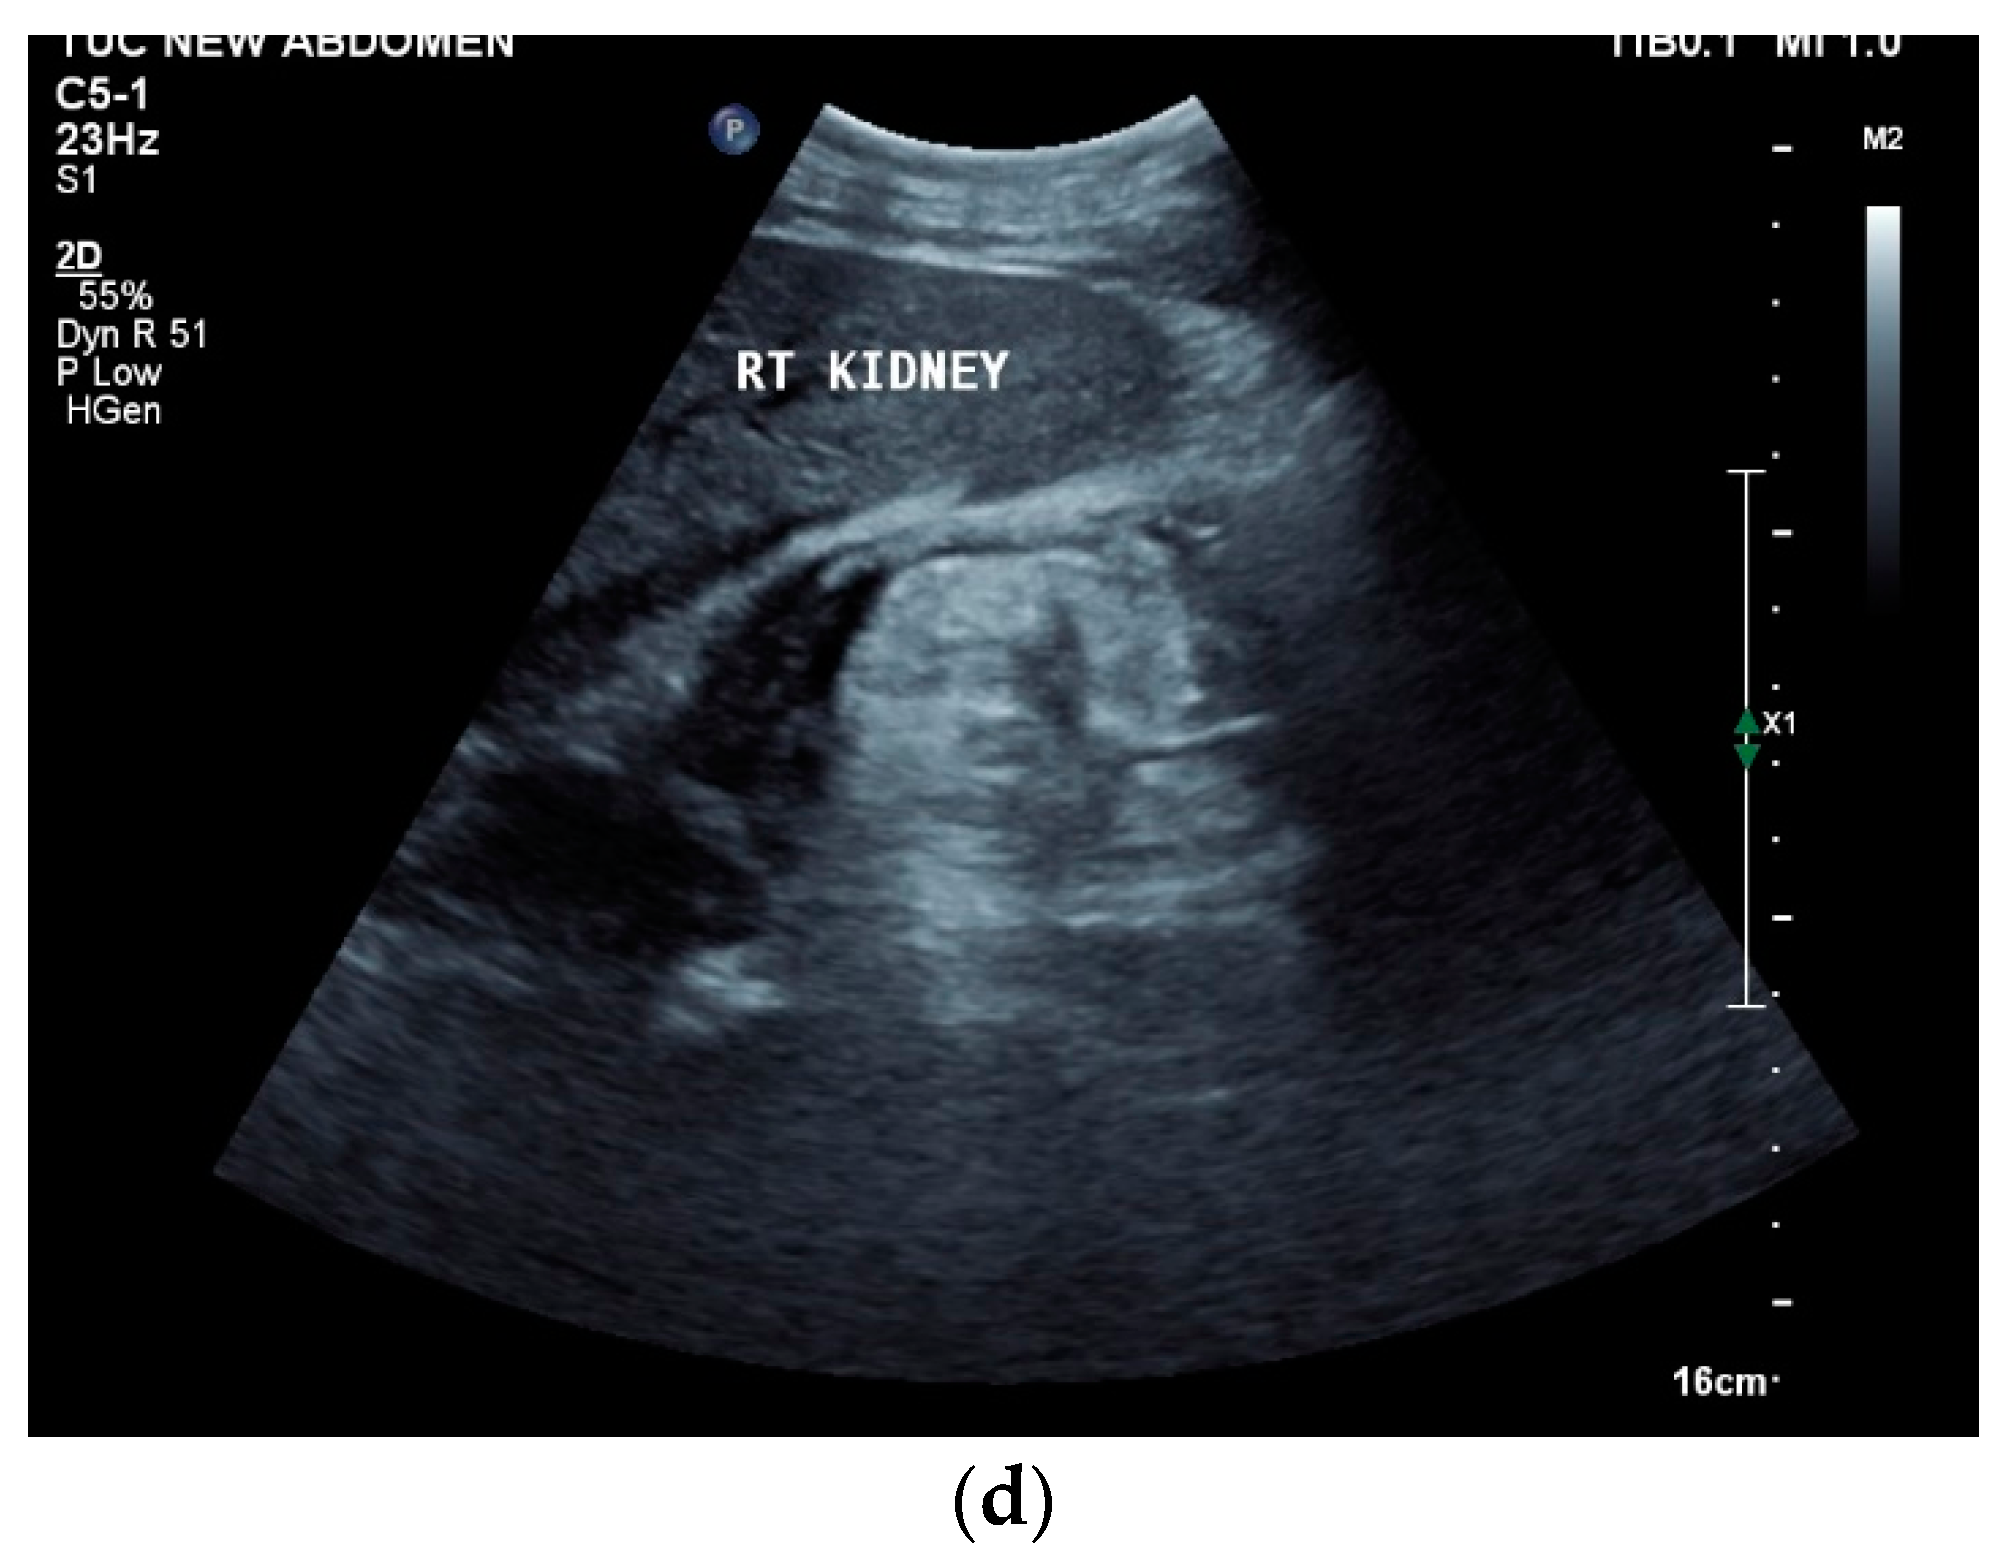

Papillary necrosis can occur, caliectasias develop in the course of the disease, and some patients develop hydronephrosis [114]. Caliectasia can present as asymmetric hydrocalicosis [115] [Figure 7a,b].

Figure 7.

Renal tuberculosis. Adjacent to the renal sinus are cyst-like lesions with smooth borders. Characteristic of caliectasias (a). Small “tubular” structures are noticeable in the kidney (arrow). The parenchyma presents nodular hypoechoic lesions. Perforation of caseous necrosis, and small intrarenal fistulas (b). “Putty kidney”—final stage of renal tuberculosis. Very small (non-functioning) kidney with highly diffused hyperechoic parenchyma (c), surrounded by a perinephritis fluid collection (d).

“Putty kidney” is a possible final stage of renal tuberculosis. The term describes diffuse parenchymal renal calcifications that can be seen on a simple X-ray, as well as a “putty-like” substance, which is found inside a surgically removed tuberculosis kidney [117,118] [Figure 7c,d].

If the ureter is affected, mucosal irregularities and ureteral dilatation due to localized or multilocular strictures must be differentiated in radiological imaging. The ureter can shorten (pipe-stem ureter) [114]. Varied effects of tuberculosis on the urinary tract are infundibular stenosis with caliectasis, moth eaten calyx, parenchymal calcification, cortical scarring, caseous mass/abscesses (with potential rupture into the perinephritic space and calyx) [Figure 7b], a hiked-up pelvis, urothelial thickening, and a beaded ureter [115].